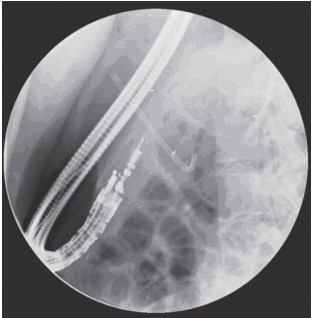

Innovative techniques such as radiofrequency ablation and brachytherapy are being explored to extend the capabilities of EUS-guided treatments further. These methods are especially considered for patients unfit for surgery or those needing palliative control of locally advanced cancers. While these advanced techniques show promising preliminary data, they remain under clinical investigation, highlighting the dynamic nature of gastroenterological research.

Although many EUS-based techniques primarily target the ablation or control of pancreatic malignancies, they also play a vital role in enhancing the delivery of radiation therapy. This is achieved through the placement of radiopaque markers directly into the tumor, facilitating targeted treatment and potentially improving outcomes for patients with various types of cancers.